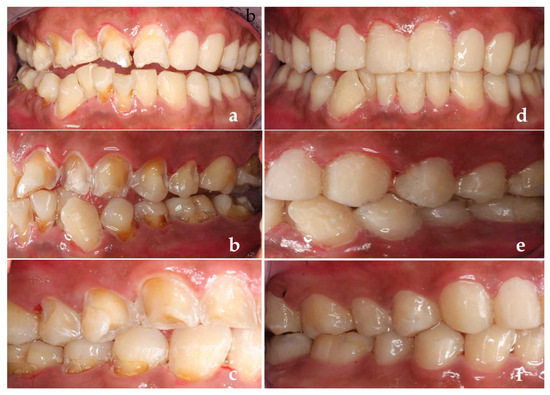

Finally, the patient was followed up for observation. The modified USPHS standard was used to evaluate the quality of restorations in this software. One year after treatment, we found that the aesthetic effect, margin fitness and color matching of the restorations were excellent. The patient had no secondary caries, but we found the poor retention of a restorative filling in tooth #22 (Figure 5a,b). It can be seen that one year after treatment, the patient’s dental health had improved, and we dealt with the problems we found in time (Figure 5c,d). Then we reassessed his caries risk and it dropped from high risk to medium risk. So, we adjusted his caries management (Figure 6a–c).

Figure 5.

(a,b) One year after treatment; (c,d) After the dentist dealt with the new problem in time.

USPHS was used to evaluate the restorations again 2 years after treatment, this time we found secondary caries in the patient’s teeth (Figure 7). We removed secondary caries and restored the cavity again in time, then he reassessed the caries risk routinely, which was still at medium risk.

Figure 7.

Two years after treatment.

However, after this return visit, the patient was lost to follow-up for 3 years. Three years later (5 years after the first treatment), the patient came back with dental plaque covering the whole tooth surface, severe periodontal inflammation, many secondary caries and the retention, margin fitness and color matching of the restorations were poor (Figure 8a). Retreatment at this time could not achieve a perfect therapeutic effect (Figure 8b) and the reassessment of his caries risk this time was high risk again.

Figure 8.

(a) Five years after treatment; (b) Retreatment completed.